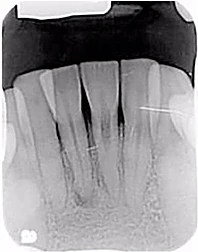

Bệnh nhân nữ 50 tuổi đến vì cơn đau ở vùng hàm trên bên phải. Cô khá chắc chắn rằng đó là một trong hai răng hàm lớn, và mặc dù bệnh nhân có túi lợi sâu ở gần phía sau xương hàm, cả vùng này đều đau khi gõ và sờ. Thăm dò nhưng không đủ thông tin để chẩn đoán. Bác sĩ ban đầu của bệnh nhân đang nghi ngờ bỏ sót ống tủy gần ngoài thứ hai của răng 16 (vì chúng ta luôn coi rằng răng này có 4 ống tủy) hoặc bỏ sốt ống tủy thứ 3/thứ 4 của răng 17 (hiện chỉ có 2 ống tủy đã được trám bít) (hình 13 và 14).

Hình 13: Phim cận chóp ca số 3

Kết quả trên phim cho thấy tổn thương tiêu lớn và mất xương nhiều ở răng 17 (Hình 15 và 16). Trường hợp này, ban đầu dự định là điều trị lại, sau đó phải chuyển sang kế hoạch nhổ răng, ghép xương và cấy implant. CBCT đã giúp bác sĩ nội nha lựa chọn điều trị tốt nhất cho bệnh nhân, kể cả điều trị đó không phải là điều trị tủy.